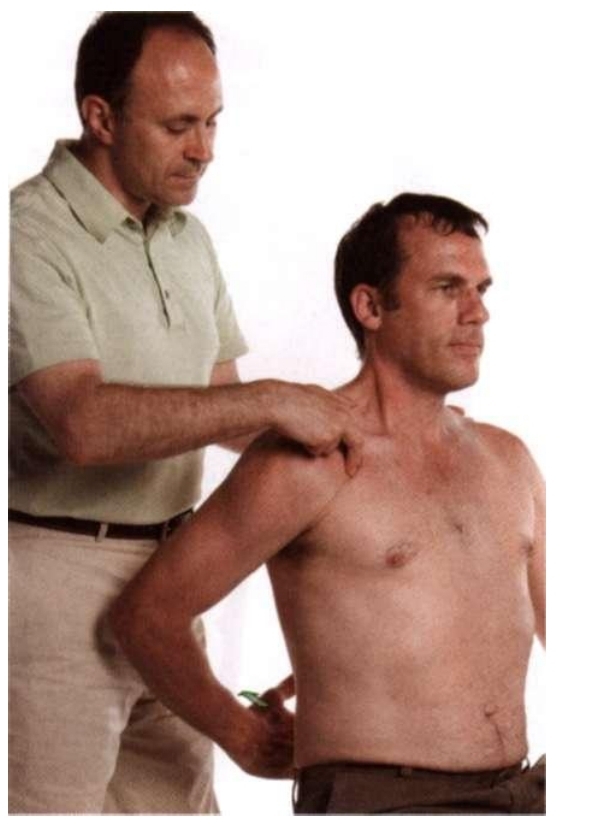

촉진 / Palpation

<시작 자세>

· 환자는 바로누운자세(supine)를 취하고 손을 등허리에 위치한다.

· 치료사는 환자의 옆에 앉는다.

· 촉진하려는 손을 환자의 어깨뼈부리돌기(coracoid process)의 바로 아래에 위치시킨다.

<촉진 단계>

· 환자에게 손과 전완으로 베드를 아래를 향하여 누르도록 지시하고, 대흉근/큰가슴근을 통하여 소흉근/작은가슴근의 수축을 느낀다.

· 계속해서 갈비뼈 부착부위까지 근섬유의 수직방향으로 촉진한다.

· 소흉근/작은가슴근 촉진을 완료시 환자에게 편안한 자세를 취하게하고 기본톤(baseline tone)을 평가하고 촉진한다.

★★★

· 환자가 베드를 손과 전완으로 아래를 향하여 누르는 이유는 팔의 폄(extension)을 유발시키며 이는 짝운동(coupled motion)인 어깨뼈의 아래쪽 돌림(downward rotation)을 유발시켜 소흉근/작은가슴근의 근수축을 유발시킬 수 있다.

소흉근/작은가슴근 수축을 유발할 때는 앉은자세가 제일 쉽다.

· 소흉근/작은가슴근의 세 섬유는 충분히 개별적으로 촉진하고 구분할 수 있다.

· 가장 바깥쪽의 근섬유를 촉진하는 대안으로는 대흉근/큰가슴근의 옆쪽에서부터 깊게 들어가 접근하는 방법인데 이는 환자에게 있어서 매우 불편하고 통증을 유발하므로 잘 사용하지 않는다.

그리고 소흉근/작은가슴근은 이러한 방법을 사용하지 않아도 충분히 촉진할 수 있느 근육이다.

<앉은 자세>

· 앉은자세에서의 촉진은 소흉근/작은가슴근을 촉진하기에 매우 용이하고 쉽다.

왜냐면 환자는 바로누운자세(supine)에서 보다 손을 등허리에 위치시키기 쉽기때문이다.

환자는 등허리에 손을 위치시키고 뒤쪽으로 손을 밀게하여 팔을 폄(extension)시켜 짝운동(coupled motion)을 통해 어깨뼈를 아래쪽돌림(downward rotation)시켜 소흉근/작은가슴근의 수축을 유발시켜 촉진을 하면 된다.